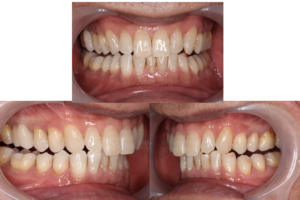

今回は30歳代男性の前歯の治療についてお話しします。

今回は前歯の色を改善する治療を行いました。

画面向かって左側に黒っぽく見える歯は既に神経がとってあり

裏側からアマルガムという薬が詰めてありました。

今回は最終的にオールセラミッククラウン(陶器でできた被せ物)で修復をする計画になりました。

もちろん、ラバーダムと顕微鏡(マイクロスコープ)、そしてMTAシーラーを用いました。

あその後ファイバーコアという材料で土台を作った後にセラミックで歯を作成します。

とても綺麗に色をしており、自然感があり、そして汚れにくく、歯との接着も強いため外れにくく隙間から

虫歯にもなりずらいのがセラミックです。

1本の歯が少しでも長く機能し続けるよう、最善最先端の治療を提供していきます。